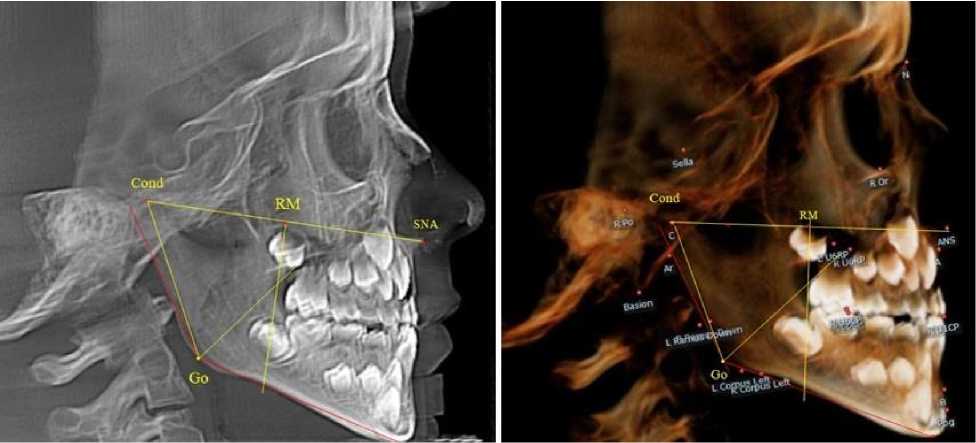

Основу анализа телерентгенограмм составляла кондиллярно-спинальная линия, соединяю- щая верхнюю точку суставной головки с передней носовой остью (Cond-SNA). На середину указанной линии ставили точечный ориентир (RM), от которого вниз проводили перпендикуляр, который, так же, как и на ортопантомограмме, ограничивал ретро молярную область (рис. 2).

а

Рис. 2. Анализ боковой телерентгенограммы (а) и 3D-модели (б) в периоде сменного прикуса

Стресс-осью для оценки положения нижнего дистального зуба (или зачатка зуба) служила биссектриса кондилярно-гониально-ментального угла ( Cond-Go-Ме ), в отличие от аналогичной оси ортопантомограммы.

При анализе боковых телерентгенограмм и трехмерной модели установлено, что положение зубов и челюстей относительно реперных линий было близким по значениям, полученным при анализе ортопантомограмм.

На середину суставной горизонтальной линии Cond-SNA ставили точечный ориентир ( RM ), от которого вниз проводили перпендикуляр, который, так же, как и на ортопантомограмме, ограничивал ретромолярную область. Зачаток первого верхнего постоянного моляра, как правило, располагался впереди ретромолярной вертикали.

Биссектриса угла Cond-Go-Ме (стресс-ось), так же, как и на ортопантомограмме, располагались позади от формирующихся зачатков первых постоянных моляров нижней челюсти (рис. 4).

Таким образом, для анализа положения зубов и оценки соразмерности челюстей в клинической практике приемлемы оба анализа рентгенограмм как ортопантомограмма, так и боковая телерентгенография.